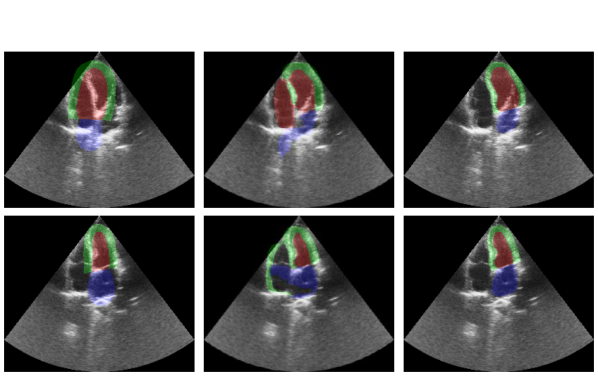

Refer to caption

(a) Median cases

(b) Worst cases

Figure 5: Case analysis and comparison of the GCN with displacement method and nnU-Net on CAMUS. The cases are selected based on the overall Dice score between the annotation and the GCN or U-Net segmentations.

We use the same criteria for anatomical correctness as Painchaud et al. [11]. The anatomically incorrect cases for the GCN are cases where the model confuses the endo- and epicardium keypoints, as in Fig. 4. Using the displacement method avoids this from happening, resulting in no anatomically invalid segmentations. Fig. 5 shows the median and worst cases of the GCN with the displacement method and nnU-Net.

While the GCN does not outperform U-Net in terms of accuracy for multi-structure segmentation, the keypoint representation has its own advantages. Both architectures have their unique data representation and solve the problem in a fundamentally different way. The pixel-wise approach of U-Net can give the most accurate segmentations, but can also produce anatomically incorrect results. On the other hand, the GCN with displacement method has lower accuracy but does not produce anatomically incorrect segmentations as the cardiac shapes are embedded as a strong bias in the network. However, the GCN can still fail to place the anatomically correct shape correctly in the image. Fig. 5(b) shows an example where both the GCN and U-Net fail to generalize to samples with reduced depth. From an abstract point of view, GCN can be seen as a heavily regularised version of pixel-wise architectures. The displacement method regularizes the architecture even further. Finally, it is worth noting that nnU-Net is an order of magnitude larger and slower than the GCN.